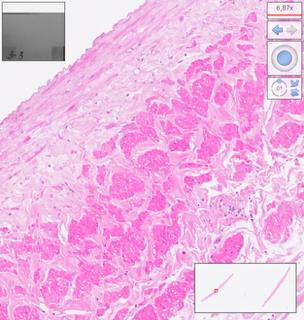

Fig. 7. Venous homograph, 7 days of preservation in RPMI 1640 solution. Hematoxylin-eosin staining, digital magnification: the endothelium is well preserved, the intima is wide, with thick collagen fibers, the myocytes of the middle layer are clearly differentiated; the well-preserved endothelium vasa vasorum attracts attention.

Fig. 8. Venous homograph, 7 days of preservation in RPMI 1640 solution. Weigert–Van Gieson coloring, digital magnification: collagen is well expressed in the form of thick fibers of purple shades.